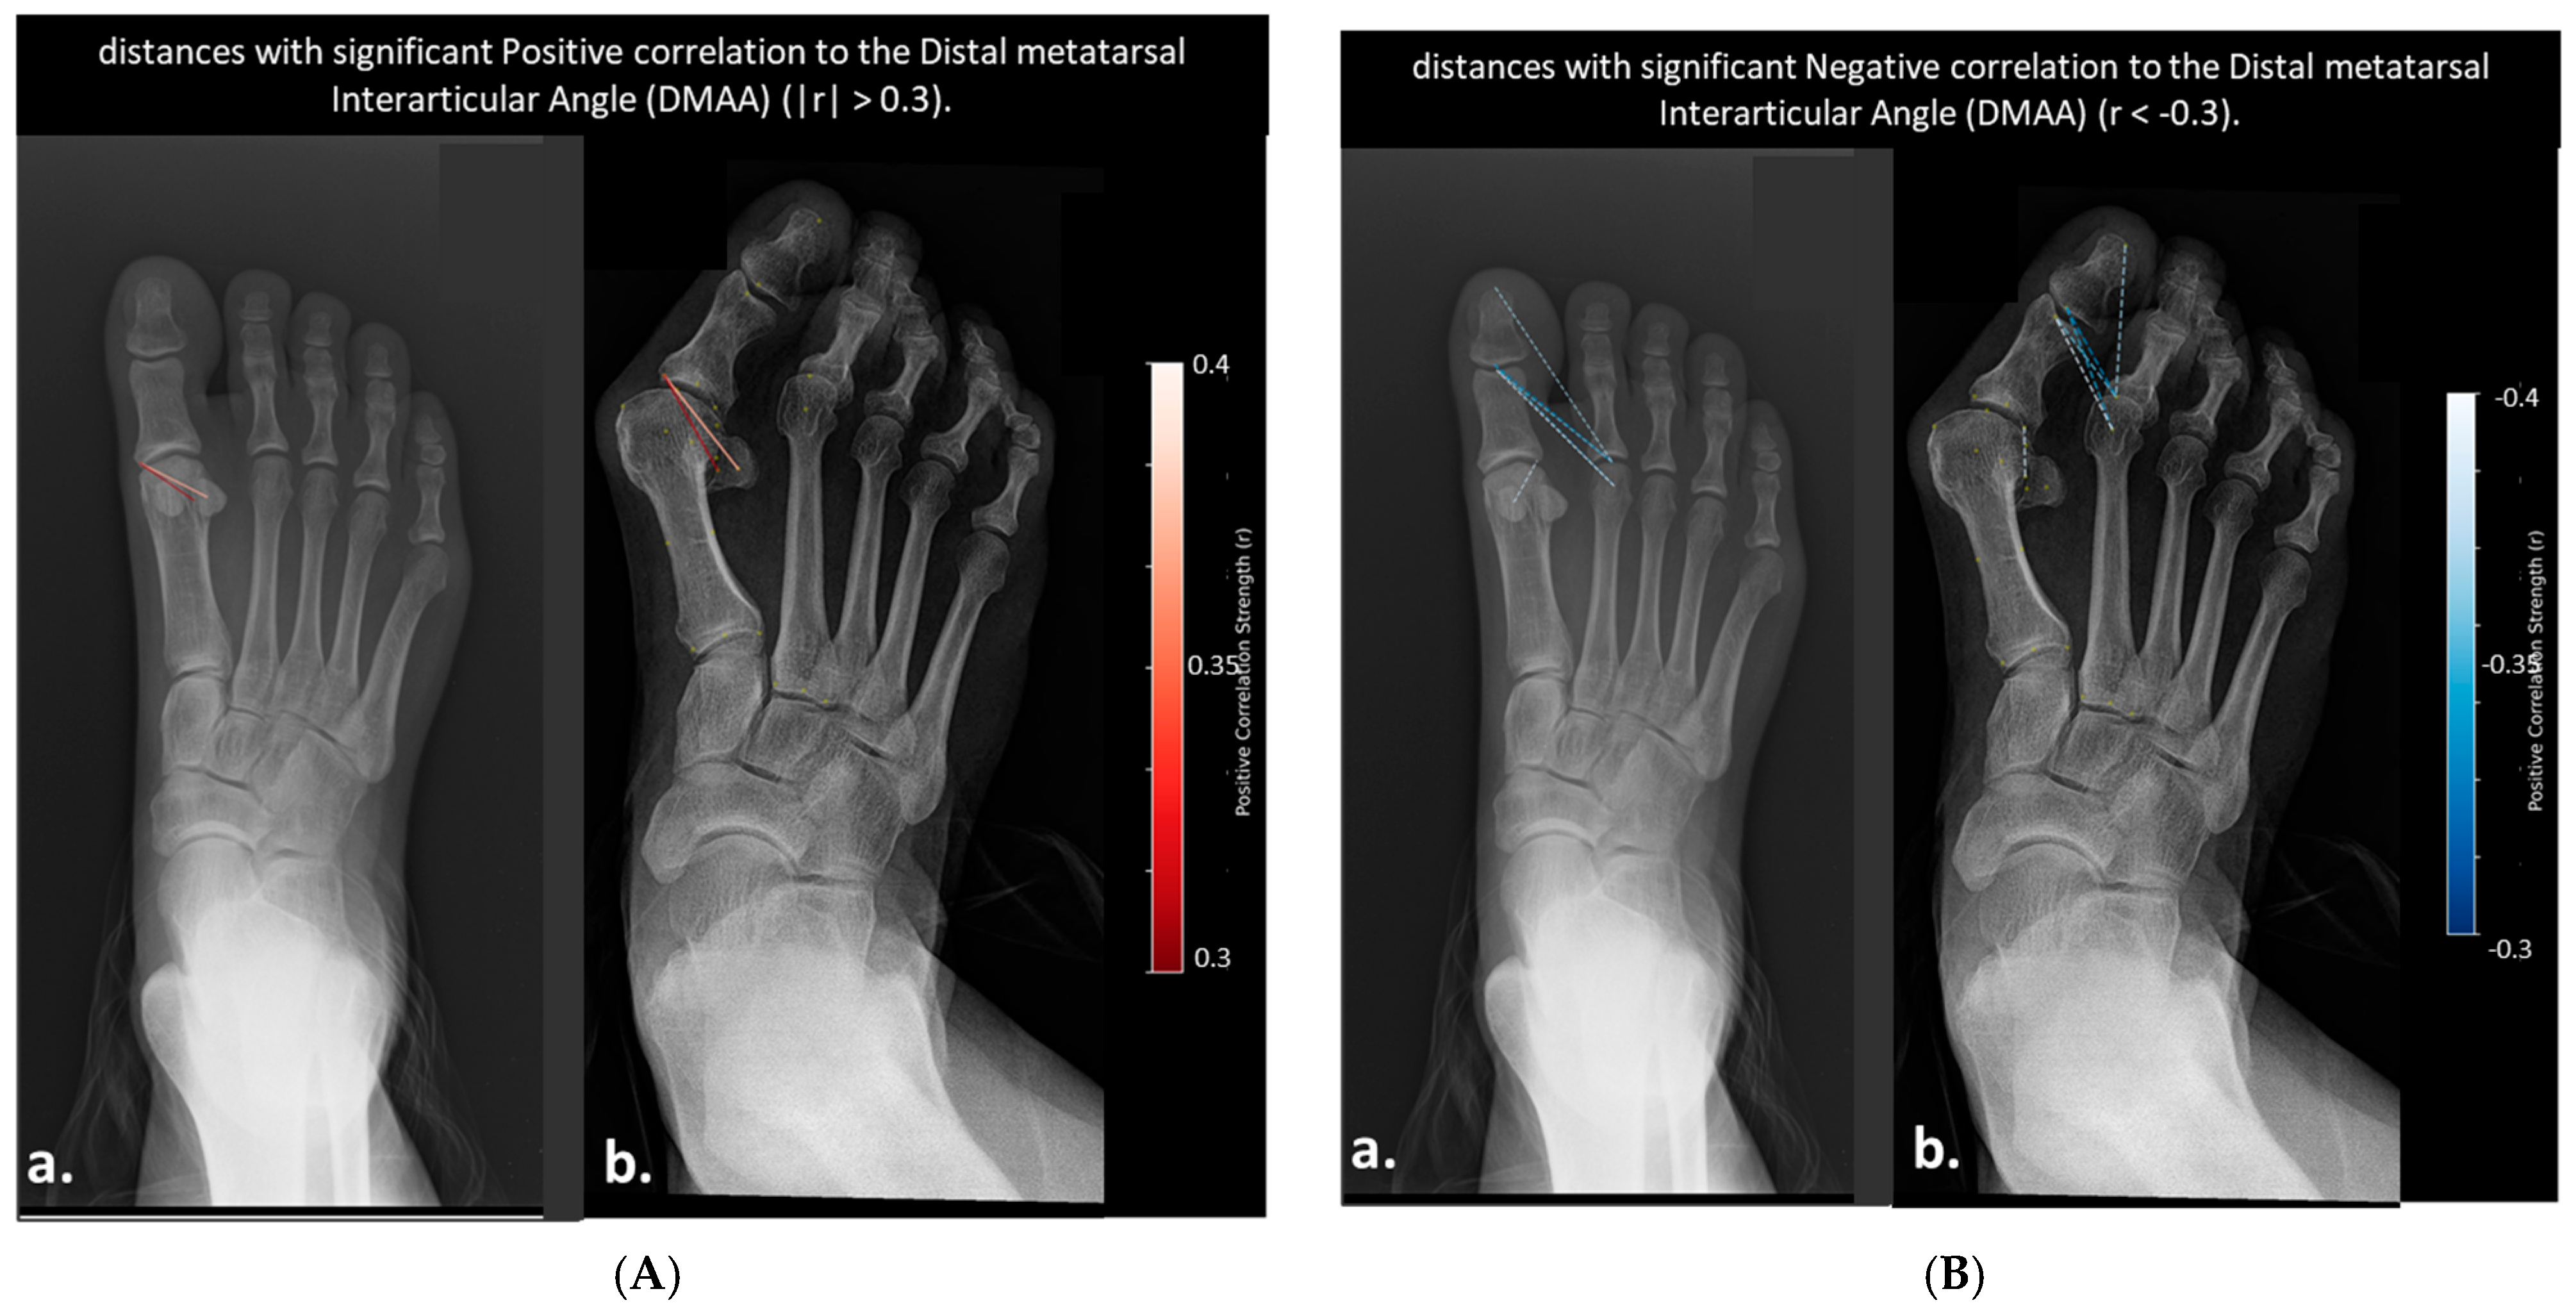

- Distances Correlated with Distal Metatarsal Articular Angle (DMAA)